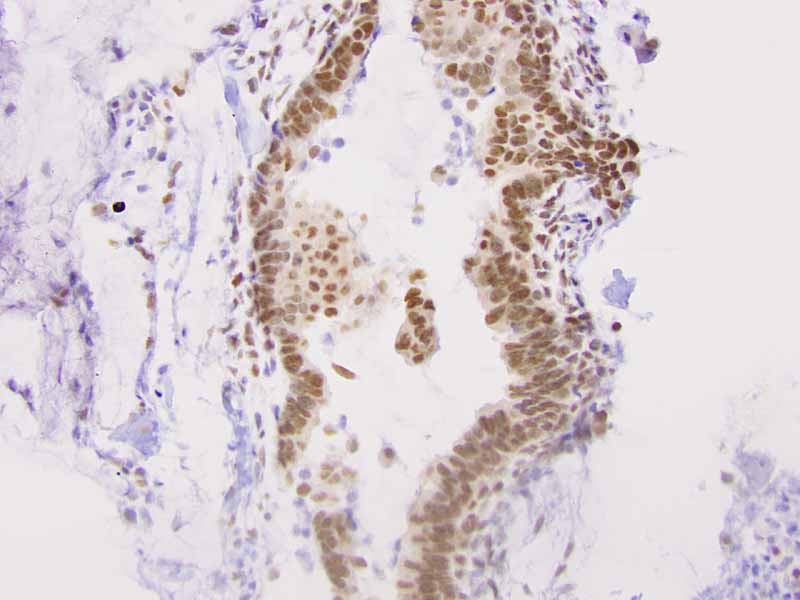

TLE-1

Immunohistochemistry: The tumor cells are also positive for cytokertin 7 and TLE-1. Positive immunoreactivity for cytokeratin 7 (Panel R) and EMA are also present extensively in the epithelial cells. The spindle cell component are positive ofr EGFR and CD99. Both epithelial and spindle cell components show positive nuclear immunoreactivity for TLE-1 (Panel S).

TLE1 is a highly sensitive but not entirely specific marker for the diagnosis of synovial sarcoma [Foo WC et al., 2011; Jagdis A et al., 2009; Terry J et al., 2007] as TLE1 is expressed in other soft tissue and bone tumors [Kosemehmetoglu K et al., 2009] including endometrial stromal sarcoma, acral myxoinflammatory fibroblastic tumor, schwannoma, liposarcoma, and others. CD99 is positive in about 60%-70% of synovial sarcomas [Pelmus et al., 2002; Olsen SH et al., 2006]. This feature can result in confusion with Ewing sarcoma.  Expression of either TLE1 or CD99 has been demonstrated in some carcinomas but co-expression of these two markers in carcinomas is rare [Zaccarini DJ et al., 2018].

EMA may well be the most sensitive marker for recognition of synovial sarcoma [Pelmus et al., 2002; Olsen SH et al., 2006]. Keratin and EMA are widely expressed by synovial sarcomas [Guillou L et al., 1997]. Expression is usually patchy rather than diffuse but epithelial components are strongly positive. The number of positive cells in monophasic fibrous synovial sarcoma can be scant and may requires extensive sampling before being demonstrated. These markers are less expressed in poorly differentiated synovial sarcomas [Van de Rijn et at;, 1999]. Because of positive immunoreactivity for S100 in some synovialsarcoma particularly the monophasic fibrous type, misdiagnosis as a malignant peripheral nerve sheath tumor can be a diagnostic pitfall. Reduced expression of SMARCB1/INI1 can be seen in synovial sarcoma regardless of whether rhabdoid changes are present [Kohashi K et al., 2010]. Synovial sarcomas are also positive for Bcl2 [Suster S et al., 1998] and calponin [Fisher C et al., 2003].

Translocation involving t(X;18)(p11.2;q11.2) translocation involving SS18(SYT) on chromosome 18  is present in over 90% of synovial sarcoma regardless of the type [Sandberg AA et al., 2002]. SS18-SSX1 is more common than SS18-SSX2. SS18-SSX2 is typically seen in monophasic fibrous synovial sarcoma and SS18-SSX1 is typically associated with biphasic synovial sarcoma [Antonescu CR et al., 2000; Kawai A et al., 1998; Ladanyi M et al., 2002]. Both translocations can be reliably detected by FISH or RT-PCR [Amary MFC et al., 2007]. TLE1 is upregulated in synovial sarcoma [Nielsen TO et al., 2002; Nagayama S et al., 2002] and TLE1 can be detected by immunohistochemistry.